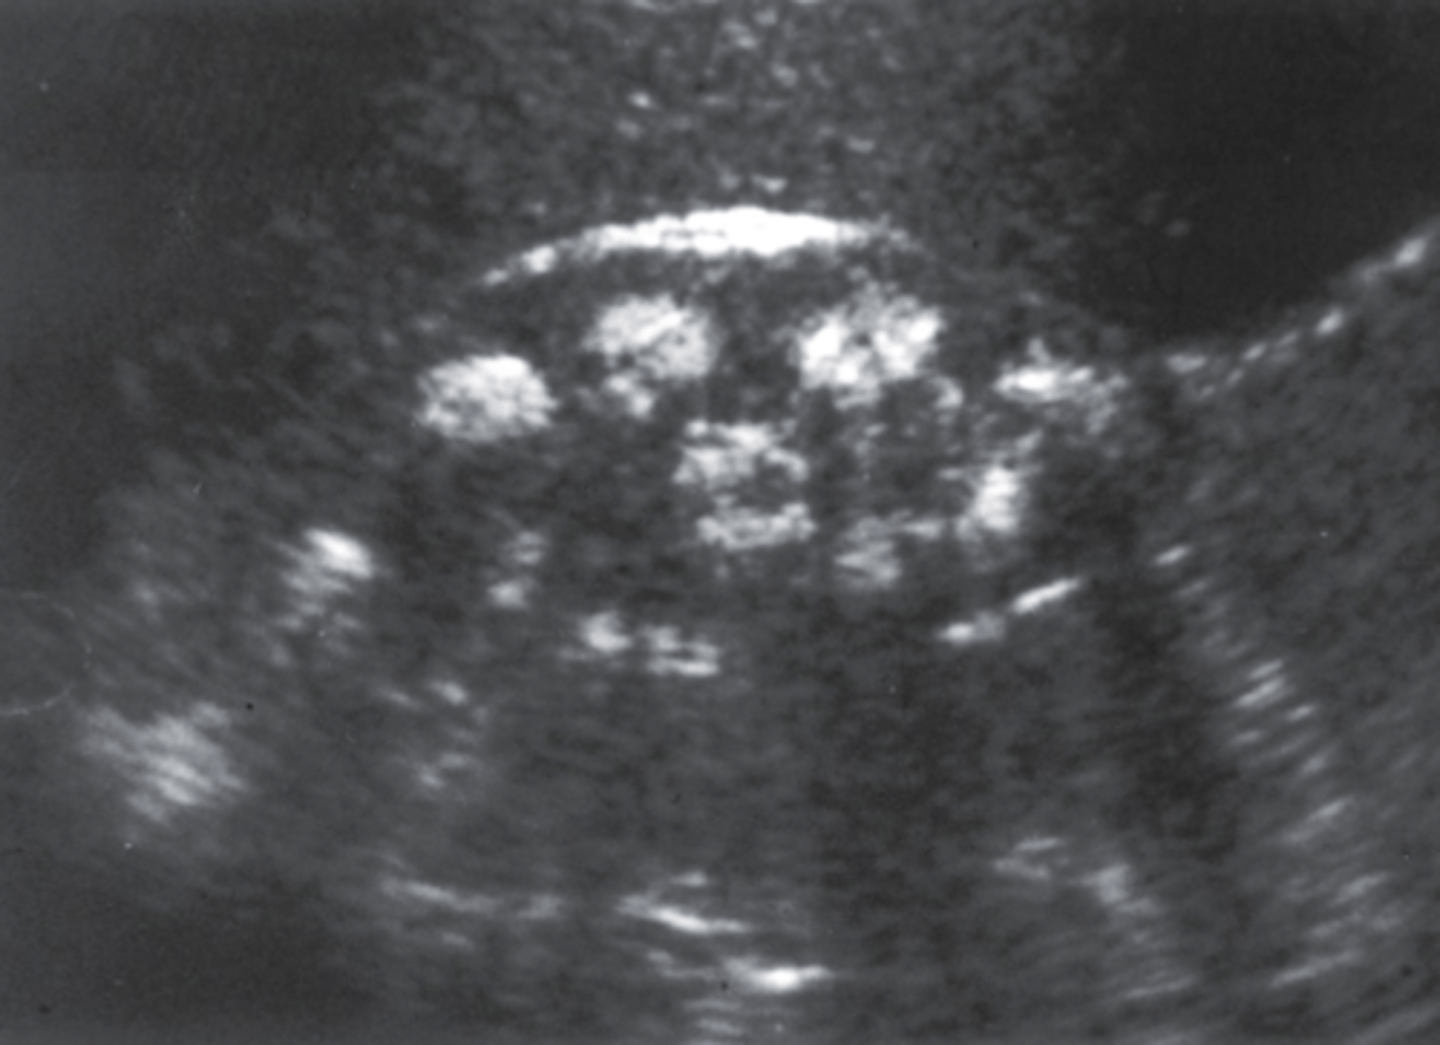

5. The 41-year-old patient in Figure 7-42 had a clinical history that included decreased renal function, urinary tract infections, and a palpable abdominal mass. What is the most likely diagnosis?

a. Acquired renal cystic disease

b. ARPKD

c. MCDK

d. ADPKD

6. Which of the following would be most likely associated with the findings in Figure 7-42?

a. Urinary tract infection

b. Testicular torsion

c. Hemihypertrophy

d. Urachal anomaly